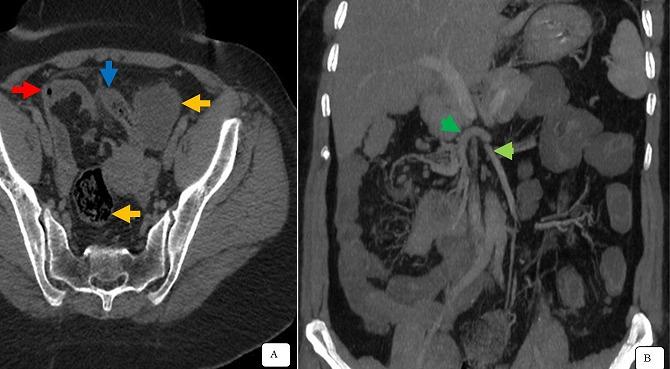

Complete common mesentery is a rare abnormality in midgut rotation. Its detection is exceptional during adulthood because, during this period, is very often asymptomatic and therefore not diagnosed. Complete common mesentery may be discovered incidentally in patients with ectopic appendicular syndrome, as in our case study. We here report the case of a 42-year old patient presenting with acute clinico-biological pelvic inflammatory disorder. CT scan allowed the diagnosis of complete common mesentery associated with acute appendicitis. Laparotomy confirmed the diagnosis of perforated acute appendicitis associated with intestinal malrotation. Appendectomy outcomes were favorable.

完整的共同肠系膜是中肠旋转罕见的异常情况。在成年期其检出极为罕见,因为在此期间它常常没有症状,因此未被诊断出来。完整的共同肠系膜可能在异位阑尾综合征患者中偶然发现,就像我们的病例研究那样。我们在此报告一例42岁患者,其表现为急性临床生物学盆腔炎症性疾病。CT扫描诊断为完整的共同肠系膜合并急性阑尾炎。剖腹手术证实诊断为穿孔性急性阑尾炎合并肠旋转不良。阑尾切除术后结果良好。